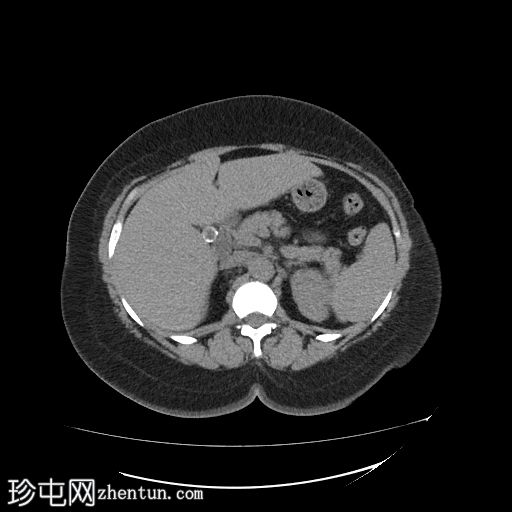

矢状位

平扫

胆囊内可见多发大小不一的多面环状钙化胆结石。胆总管直径处于正常上限。胆总管内未见其他结石。

右侧肾中盏可见一非梗阻性结石(10.5 mm),CT值较高(900–1000 HU)。